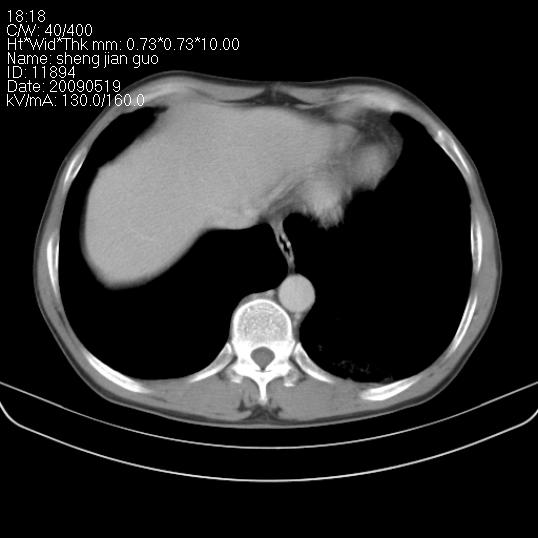

以下是引用zjzjr在2009-5-19 17:25:00的发言:[br]支持楼主考虑,另左肺下叶阻塞性炎症。

以下是引用zhao_bin2008在2009-5-19 17:48:00的发言:[br]支持左肺下叶周围型肺癌并阻塞性肺炎。

以下是引用zsl6918在2009-5-20 7:10:00的发言:[br]左侧中心型肺癌!